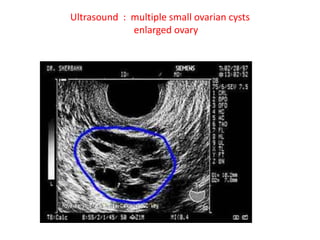

• USG-PCO > 12 FOLLICLE IN EITHER OVARY

MEASURING 2-9mm diameter/.10ml VOLUME

Ultrasound : multiple small ovarian cysts

enlarged ovary